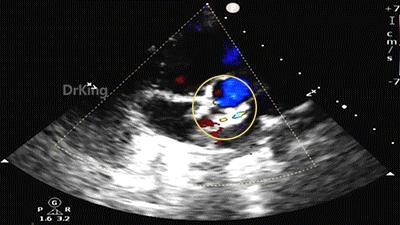

完全释放后超声下观察

主动脉短轴切面显示封堵器呈Y字型抱住主动脉根部,夹持稳定。

封堵器形态良好,未见分流,封堵成功。